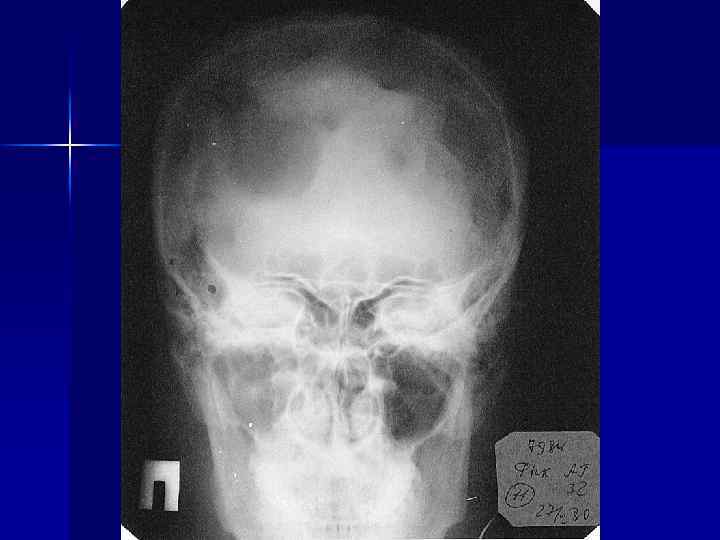

Диагностика n n n - Лабораторная диагностика Пункция лимфоузлов и поиск клеток Березовского-Штернберга При подозрении на поражение того или иного органа проводятся следующие исследования: Rg-графия и КТ грудной клетки Rg-графия и КТ плоских костей УЗИ органов брюшной полости (печень, селезенка, почки, лимфоузлы), КТ живота Рентгеноконтрастная лимфография Rg-графия кишечника (ирригоскопия) ФГДС Исследование функции печени и почек лапаротомия

Диагностика (продолжение) - Rg-диагностика костей: • множественно-очаговая форма (70%) • диффузно-поротическая (20%) • солитарная (5%) • остеосклеротическая (5%) - по показаниям Rg-диагностика и УЗИ внутренних органов